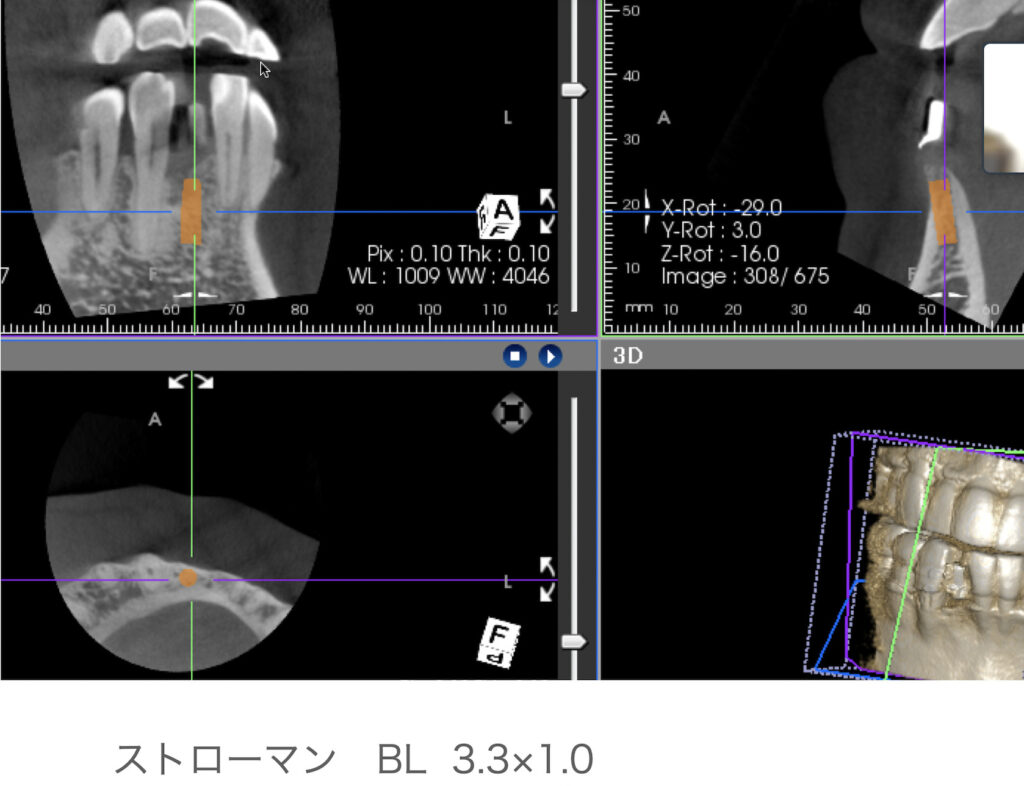

内容は、骨造成を伴うインプラント治療についてです。実際発表することにより、プレゼンスライドの不足に気づくのでいい機会になりました。

内容は、骨造成を伴うインプラント治療についてです。実際発表することにより、プレゼンスライドの不足に気づくのでいい機会になりました。